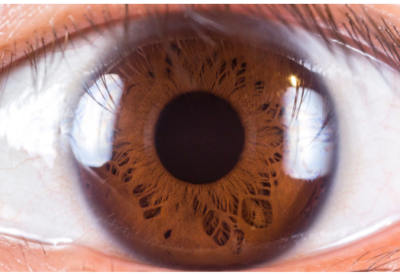

In August 2013, the International Centre for Eye Health developed a similar app called Peek (Portable Eye examination Kit). This app uses the camera’s flash light to light up the back of the eye called the retina in addition to using the cell phone’s camera to check the eye lens for cataract. This also tests visual fields, colour vision, contrast sensitivity and can record the patient’s exact location and mail the results to eye doctors.

In September 2013, Researchers from Massachusetts Eye and Ear Institute in Harvard Medical School have developed a new app which helps capture high quality photos of the retina. Earlier studies which relied on the built in camera app in iPhones gave poor results since one could not control the focus independently. This system overcomes this drawback by using the app called ‘Filmic pro’ which allows the user to control focus, light intensity and exposure. This app is used along with a 20D lens. If used with an additional lens (called the Koeppe Lens), better results are obtained, even though the images obtained from the 20D lens alone were excellent.